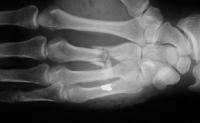

Final result, eight months postop, healed:

Healed.